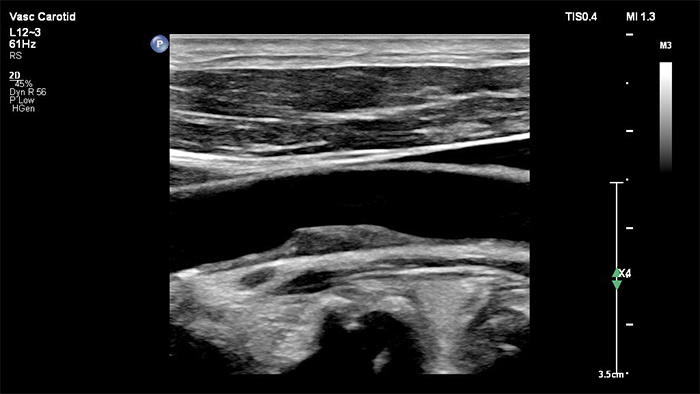

Il trasduttore XL14-3 xMatrix offre imaging xPlane che va oltre l'approccio convenzionale agli esami vascolari grazie a immagini in tempo reale acquisite contemporaneamente sul piano longitudinale e trasversale. Vantaggio principale: l'imaging xPlane elimina la necessità di ruotare il trasduttore per acquisire viste ortogonali. Con un semplice movimento della trackball è possibile svolgere una valutazione anatomica completa, risparmiando tempo durante l'esame.

Il trasduttore XL14-3 xMatrix offre inoltre funzionalità Doppler xPlane. Il Doppler a onda pulsata (PW) xPlane consente un posizionamento preciso del volume del campione Doppler utilizzando contemporaneamente le immagini di riferimento longitudinale e trasversale. Vantaggio principale: il Doppler xPlane riduce gli errori di posizionamento del volume del campione e fornisce maggiore riproducibilità e coerenza durante il campionamento di stenosi significative.